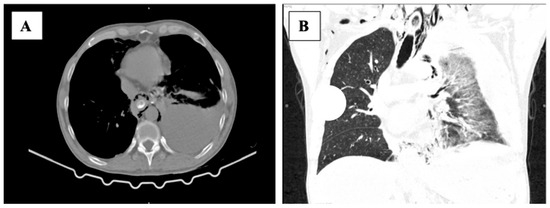

In an era where patient-reported outcomes have become more important, one of the tools that every surgeon should have in their bag is diagnostic laparoscopy. This versatile instrument can serve as a diagnostic confirmation and definitive treatment. Through a couple of trocars placed into the abdomen, a surgeon can diagnose a variety of surgical ailments, such as bowel infarction, the site of obstruction in bowel obstruction, occult hernias, and, last but not least, trauma. In addition, the oncological field is another place where it shines: intraperitoneal tumors, peritoneal carcinomatosis, and superficial liver metastases that were not identified upon imaging. Staging laparoscopy is recommended for pancreatic and gastric cancers, thus providing a potential indication for radical surgery. Laparoscopy is not only diagnostic, but after identifying the nature of the surgical disease one can perform various laparoscopic surgeries with net advantages when compared to the open approach.